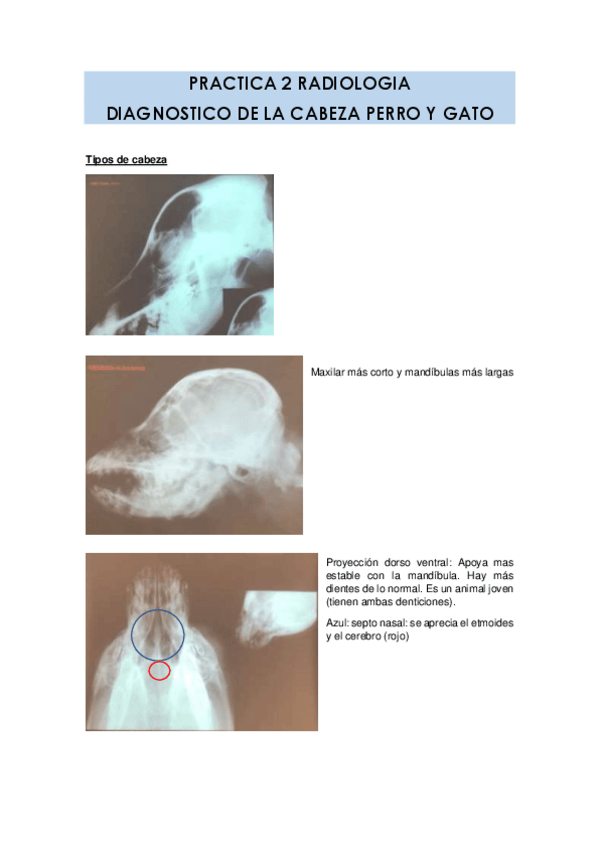

PRACTICA-2-RADIOLOGIA.pdf